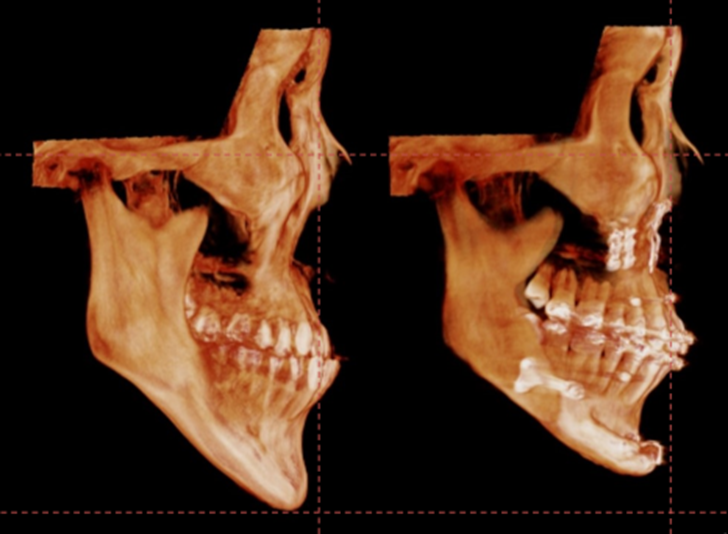

아랫치아가 앞으로 나와 있는 3급 부정교합이지만

상대적으로 턱끝은 뒤로 들어가 보이는 경우입니다.

이런 경우에 치아를 맞추고 나면 턱끝은 심하게 뒤로 들어가 보이게 되고

이를 보상하기 위해서는 턱끝 전진량이 꽤 많을 수밖에 없습니다.

턱끝을 2단으로 절골하여 가운데 뼈를 제거하는 샌드위치 테크닉으로

턱끝의 길이를 5mm 줄이면서 앞으로 6mm 전진 시켰고,

단차가 생긴 뒷부분의 하악 하연을 매끄럽게 잘라낸 후 잘 다듬어서

앞턱 전체를 감싸면서 체부볼륨이 증가 될 수 있도록 이식하였습니다.

수술 3개월이 경과한 시점에 촬영한 CT입니다.

이식한 뼈는 자연스럽게 리모델링 되면서

거의 흡수 없이 잘 생착 된 상태로 회복하였습니다.